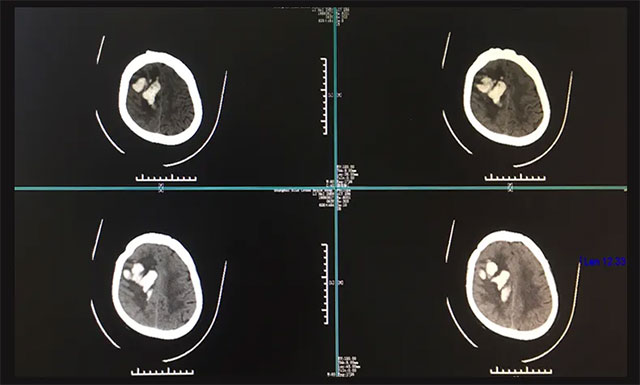

隨后,曹先生緊急撥打120電話急救,遂將患者送至當?shù)卣憬∧翅t(yī)院進行救治,在該院緊急行頭部CT檢查,影像提示:患者右側顳頂葉腦出血,兩側側腦室后角少量積血。鑒于患者當時出血量很大,約為50ml,病情又比較嚴重,生命危急,應及早手術,但因各方面條件所限,該醫(yī)院當時予以保守治療,并建議患者家屬轉(zhuǎn)院。

入院后,完善其各項檢查,為了進一步確定患者目前出血的具體情況,進行了頭部CT檢查,根據(jù)影像檢查結果,與之前在他院CT結果相比,血腫量較前增多,右側額顳頂葉出血灶(偏急性期)。經(jīng)過會診,潘仁龍主任和吳治群博士一致認為患者腦出血嚴重,處于昏迷,左側肢體偏癱,病情危急,需及早手術清除顱內(nèi)血腫,否則生命會有危險。